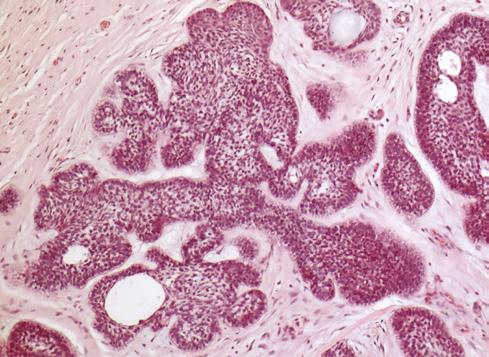

Os padrões histopatológicos mais frequentes dos AMs são o folicular e o plexiforme². Outros padrões, como o acantomatoso, de células granulosas, de células basais e desmoplásico, embora raros, podem também ser observados. A histopatologia do ameloblastoma consiste basicamente na proliferação de células epiteliais que se dispõem em padrões variáveis, que, por vezes, se fazem presentes no mesmo tumor.

Paciente do sexo masculino, 22 anos de idade, procurou o Serviço de Cirurgia e Traumatologia Bucomaxilofacial do Hospital das Clínicas da Universidade Federal de Minas Gerais, para avaliação de lesão assintomática em mandíbula. Ele relatou ausência de sintomatologia álgica, parestesia, hipoestesia ou disestesia, e não apresentava comorbidades. Ao exame físico extrabucal e intrabucal, não foram detectadas alterações dignas de nota (Fig. 1A). Entretanto, o exame tomográfico revelou extensa imagem hipodensa na região de sínfise e corpo esquerdo de mandíbula, multiloculada, com aspecto de destruição e expansão óssea, e associada aos dentes 31, 32, 33, 34, 35 e 41 (Fig. 1B). Uma biópsia incisional confirmou a hipótese diagnóstica de AM convencional (Fig. 1C). Por meio de um acesso cirúrgico intrabucal e sob anestesia geral, o tumor foi removido através de uma ressecção marginal mínima da mandíbula, com margem de segurança óssea variando entre 5 e 10 mm, preservando a borda inferior mandibular, e exodontia dos elementos associados, além do dente 42 (Fig. 1D). Terapias coadjuvantes, como ostectomia periférica em toda extensão da lesão e aplicação de solução de Carnoy (3ml de clorofórmio, 6ml de álcool absoluto, 1ml de ácido glacial acético e 1g de clorito férrico), durante 5 minutos, foram realizadas em toda loja cirúrgica. Após um período de 4 anos de controle pós-operatório, com consultas trimestrais no primeiro ano, semestrais no segundo, e anuais a partir do terceiro ano, não foram observados, em exames clínicos e de imagem, sinais de recidiva da lesão. O paciente foi, então, submetido a um procedimento de reconstrução mandibular, que consistiu na colocação, por meio de um acesso cirúrgico extrabucal (submentoniano), de um enxerto livre autógeno de crista ilíaca, fixado com placas de titânio do sistema 2.0 (Fig. 2). Transcorridos cinco meses da enxertia, a região foi reabilitada por meio de uma prótese dentária implantossuportada, utilizando-se quatro implantes: três implantes plataforma Cone Morse de 3,75 mm de diâmetro por 13 mm de comprimento, na área enxertada; e um implante na posição de molares, plataforma Cone Morse, de 5 mm de diâmetro e 11 mm de comprimento (Fig. 3A e 3B). Após nove anos da cirurgia para a ressecção tumoral, observou-se ausência de sinais de recidiva e o paciente encontrava-se satisfeito com o resultado do tratamento (Fig. 3B e 3C).

Figura 1: A) Aspecto intrabucal pré-operatório, evidenciando aspecto de normalidade. B) Tomografia computadorizada mostrando uma imagem hipodensa, bem delimitada, multilocular, em região de sínfise e corpo esquerdo de mandíbula. C) Lesão composta por ninhos e cordões de células epiteliais odontogênicas com padrão de crescimento sólido. Individualmente, as células epiteliais, na periferia, eram colunares, hipercromáticas, dispostas em paliçada e semelhantes a ameloblastos. Na porção central, as células tinham disposição frouxa, semelhante ao retículo estrelado do órgão do esmalte. Nota-se, em áreas focais, degeneração cística. O estroma foi representado por tecido conjuntivo fibroso e pouco vascularizado. D) Ressecção marginal da mandíbula, com preservação do osso basilar.